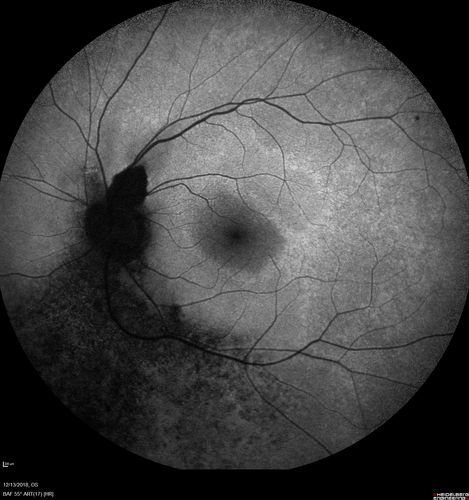

Retinitis Pigmentosa with Cystoid Macular Edema responsive to topical carbonic anhydrase inhibitors

67 year old female  She thought it was time to have her glasses changed.She has no family history of reitnal disease and has never been diagnosed with a problem.   She started having night vision trouble the last year.  Two sisters and a brother with normal vision.